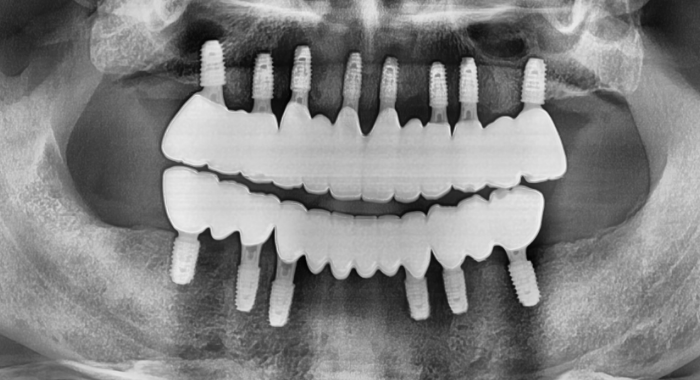

자연치처럼 편안한 풀아치(All-on-4, All-on-6)로

한 번의 수술로 편안한 식사와 밝은 미소까지 되찾아드립니다.